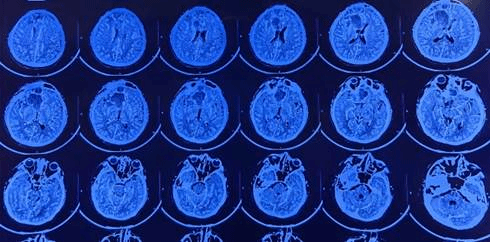

脑脓肿形成时CT(图5)脑脓肿形成时磁共振(图6)

患者术后症状改善2天后再次加重,复查CT和磁共振提示脑脓肿形成(见图5、图6)。术后第5天,在神经外科沈红教授指导下,神经外科刘利教授和殷一博主治医师为患者行机器人辅助下脓肿穿刺抽吸和Ommaya囊置入手术,术中共抽出紫褐色脓液35ml(见图7)。